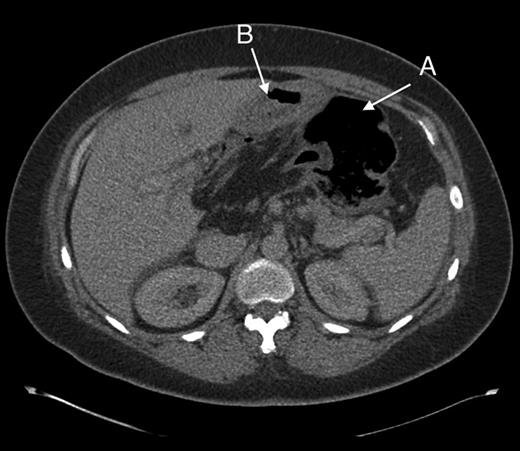

Computed tomography was used for diagnosis. Although initially reported as caecal volvulus, in hindsight there were features indicative of the herniation. (Figs 2 and 3).

Axial section through upper abdomen showing (A) distended caecum and (B) behind the stomach.